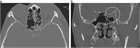

1. 造影CT(CTAngio)検査についてテキスト、画像を追加した。